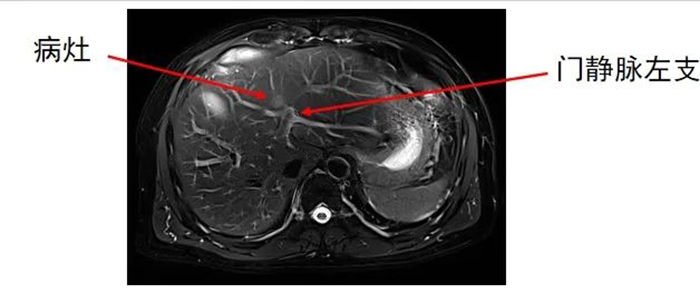

肝内转移灶数目为两个,分别位于左叶和右叶。

准确插入到病灶内,并避开了门静脉左支及分支,避免了出血并发症。